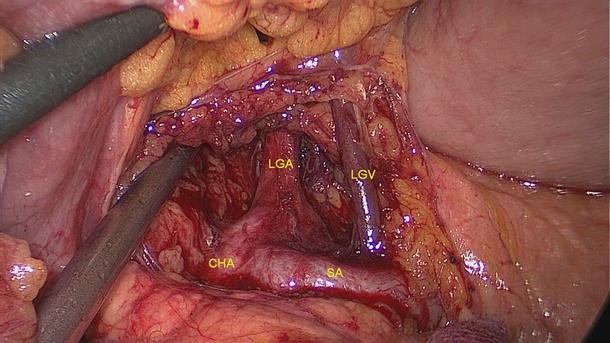

Of the 2,111 gastric cancer patients who underwent radical resection, 6 had the rare anatomic variant of the LGV patients (Figs. 4, 5, 6, 7); the incidence of this finding was about 0.28 %. Its specific drainage pattern differed from that of the normal LGV. In patients with the variant, small vessels from the anterior and posterior walls of the lesser curvature of the stomach drained into the LGV. It lay close to the LGA in the large part of the lesser curvature, descended along the gastropancreatic fold, ran across the dorsal side of the splenic artery and drained into the splenic vein. These vascular anatomies in six patients were documented by the high definition images during laparoscopic-assisted radical gastrectomy.

Fig. 6

figure 6

LGV running across the dorsal side of the splenic artery. LGV left gastric vein, LGA left gastric artery, CHA common hepatic artery, SA splenic artery